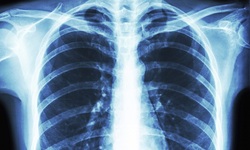

به گزارش آوای نشاط، و به نقل از دیلی میل، بنابر گزارش‌ها سی تی اسکن چهار روز زودتر می‌تواند به پزشکان در شناسایی بیماران مبتلا به کرونا ویروس کمک کند چراکه پزشکان توسط آن می‌توانند میزان تخریب بافت ریه افراد مبتلا به این بیماری را به راحتی مشاهده کنند.

محققان می‌گویند که این تشخیص سریعتر می‌تواند به آنها کمک کند تا فرایند قرنطینه کردن بیماران را زودتر و پیش از ظهور دیگر علائم این بیماری آغاز کنند. آنها با سی تی اسکن می‌توانند میزان تخریب بافت ریه افراد را مشاهده کنند و این کاری است که توسط اسکن‌های دیگر مانند اسکن اشعه ایکس قفسه سینه امکان‌پذیر نیست. بنابر گفته پزشکان ظاهرا ریه بیماران مبتلا به کرونا الگو و نشانه خاصی دارد که با بررسی سی تی اسکن می‌توان این بیماری را چند روز زودتر تشخیص داد.